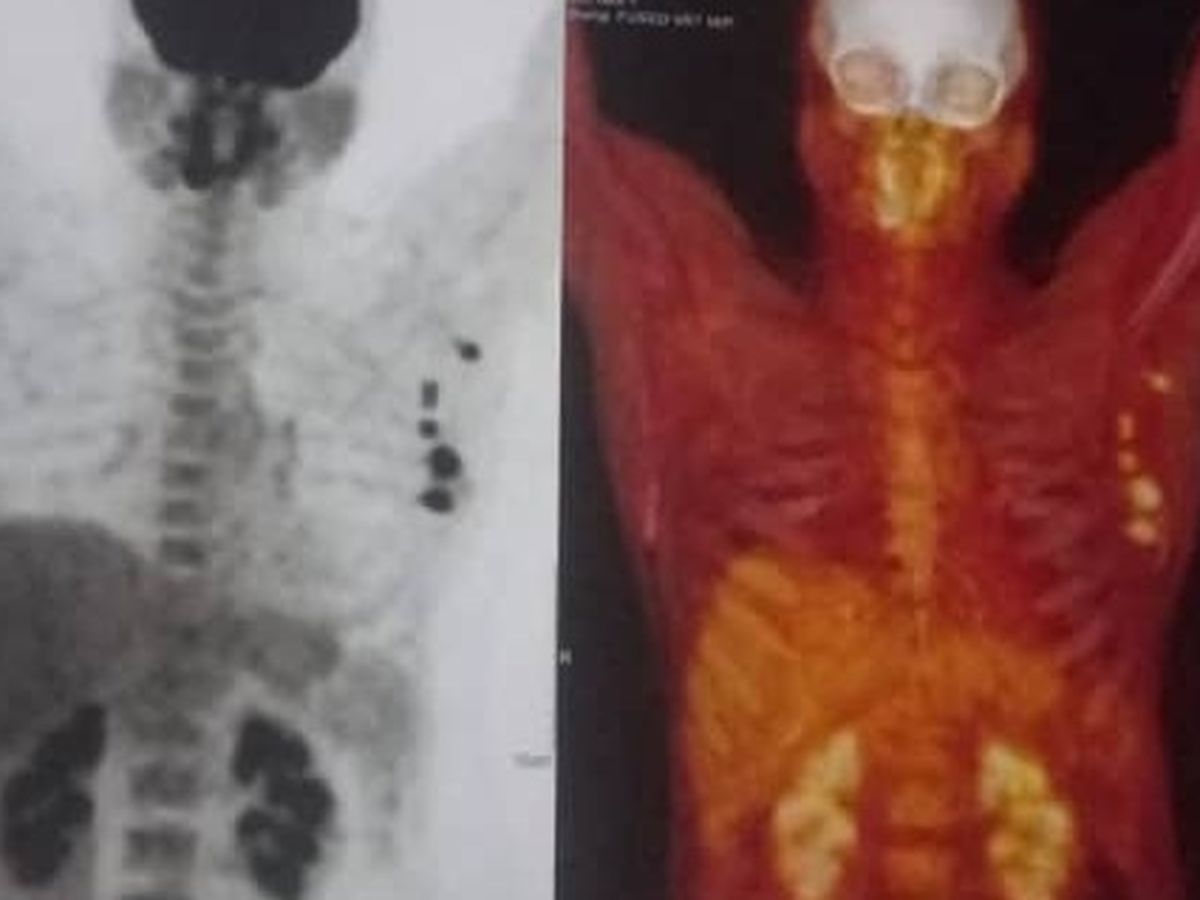

Recently, Maria was diagnosed with Stage 3 Breast Cancer. The words no one ever wants to hear. Her treatment is aggressive and urgent: she requires a mastectomy (surgical removal of her breast) followed by intensive chemotherapy. The physical and emotional toll of this alone is unimaginable.